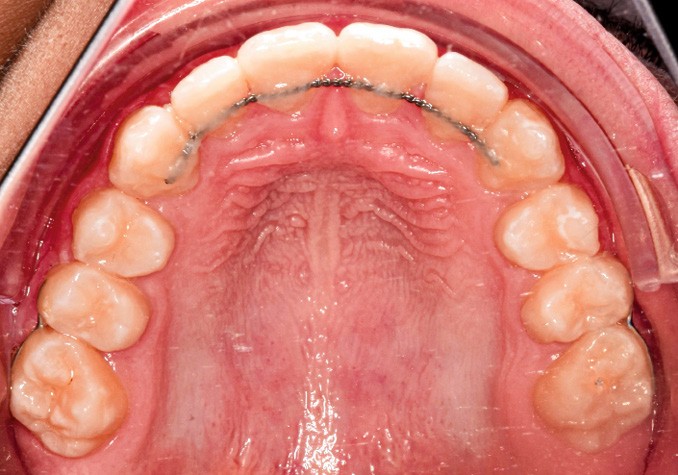

En complément des fils de contention 3-3 bimaxillaires, des contentions (fils collés acier 0.16 x0.22) ont été réalisées entre 15-17, 25-27, 35-37 et 45-47. L’objectif était d’éviter une réouverture des espaces post mésialisation.

Une sur-correction de la rotation de 17 aurait été souhaitable pour optimiser l’alignement et les rapports occlusaux (fig. 2a-d).